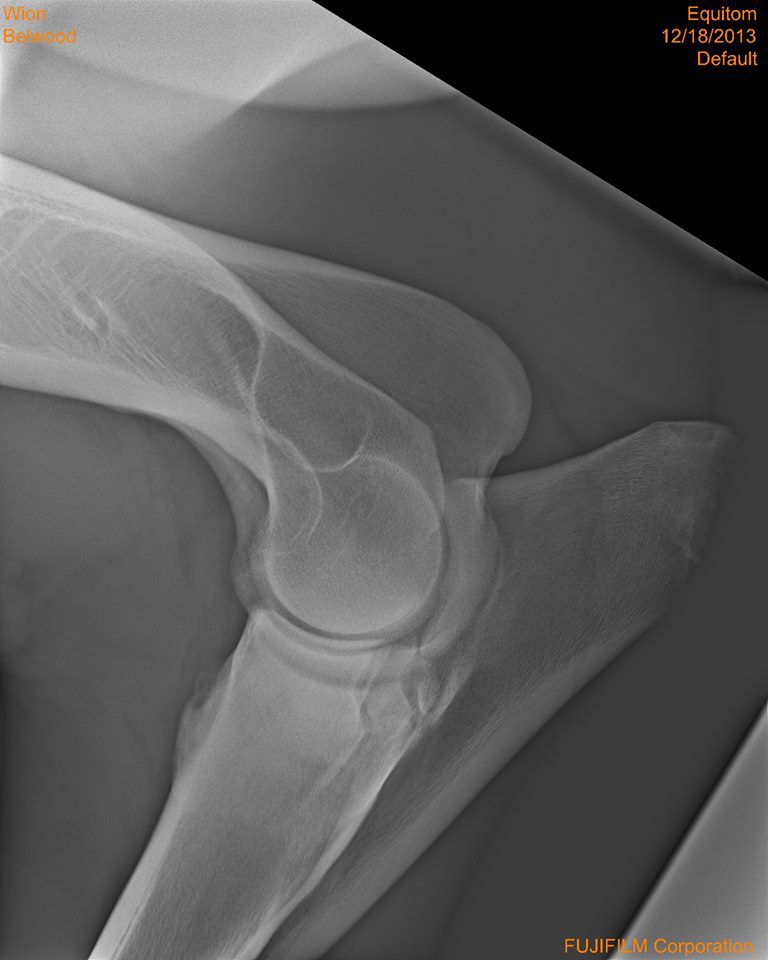

Par conny : le 31/12/13 à 14:11:27

| Dire merci | bon me revoilà avec les radios dites-moi ce que vous en pensez... |

| Dire merci | Je n'y connais pas grand chose, mais il n'y a pas une fracture là où se loge "la boule" de l'articulation ( vers le milieux ) ? Je trouve que c'est bizare à cet endroit... Message édité le 31/12/13 à 14:48 |

| Dire merci | Quercy: je vois ce que tu veux dire mais je suis comme toi, j'y connais rien... nats: comme déjà ecrit, le 1er veto a dit que le cheval n'avait "rien" et le 2eme qu'il fallait l'euthanasier... ici je sais que Al est veto et je pense qu'il doit y en avoir d'autres...donc je prefere voir avec les personnes de confiance, car mon amie ne veut pas euthanasier son cheval et si possible, le donner en tant que tondeuse à gazon... |

| Dire merci | comme déjà ecrit, le 1er veto a dit que le cheval n'avait "rien" et le 2eme qu'il fallait l'euthanasier... Sur les mêmes radio, ces 2 diagnostiques si différents? Et le deuxième véto a forcement commenté les radios avant de proposer l'euthanasie Chez ma jument de 5 ans, le premier véto m'avait aussi dit qu'il n'y avait rien de visible sur les radio malgré le fait qu'elle était positive au test de flexion et lors des radios prises en clinique, il était à (peine) visible qu'il y avait UN bec de perroquet. ça ressemblait un peu à la petite pointe floue à gauche qu'on voit sur ta 2 ème radio, mais bon entre un truc flou anormal et au autre normal... |